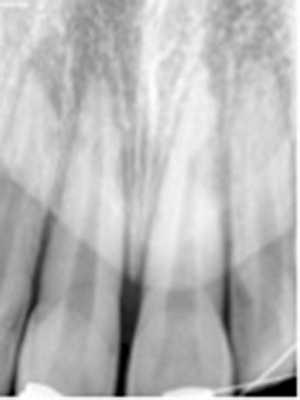

Рис. 5. Измерение расстояния от ЭЦГ до альвеолярного гребня в области зуба 2.3 (без рецессии). В данном случае показатели на 3 реформатах составили: 2,72; 3,04; 3,20 мм.

Толщина десны в исследуемой группе была меньше, чем в контрольной: соответственно 0,85 [0,7; 0,95] мм и 0,95 [0,8; 1] мм (см. рис. 3). В группах выявлены достоверные различия (p <0,05). Кроме того, толщина десневого края в обеих группах составляла менее 1 мм и по этому параметру можно считать десну «тонкой» (см. рис. 4). Рис. 4. Измерение толщины десны; использование ретрактора позволяет отодвинуть мягкие ткани губ от альвеолярного отростка.

Перед оценкой данных проводили настройку коррекции яркости и контрастности для максимальной визуализации вестибулярной костной пластинки, а также центрирование осей координат по вертикальной оси зуба для стандартизации прохождения среза.

Для повышения точности исследования проводили 3 вестибуло-оральных реформата относительно центральной оси с шагом 0,5 мм.